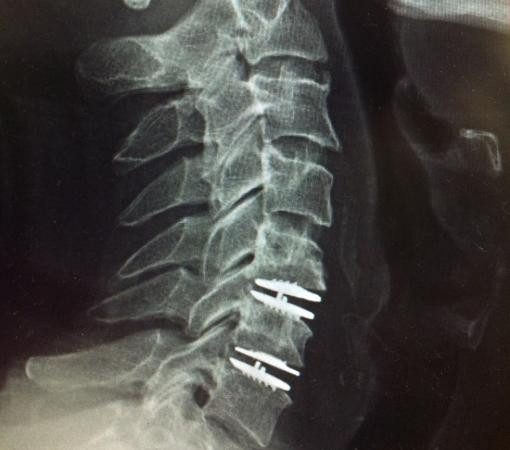

This procedure replaces the damaged spinal disc with an artificial one, allowing the spine to function normally and reducing pain. Amit was hesitant but decided to go ahead after understanding the benefits. Today, he leads an active, pain-free life.

Disc replacement surgery in Mumbai is a minimally invasive procedure where surgeons remove the damaged disc and insert an artificial one. The advanced techniques used at Synapse Spine ensure minimal recovery time and long-term relief.